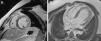

Case reportA 19-year-old male with no relevant medical history, besides having been diagnosed two weeks previously with Crohn's disease for which he was medicated with mesalamine 1500 mg twice a day and budesonide 9 mg daily, was admitted to the local hospital with retrosternal chest pain radiating to the left arm. He reported no accompanying symptoms and no relieving or aggravating factors were identified. The patient had no reported previous infection. The physical examination was unremarkable and there were no signs of hemodynamic instability or heart failure. The initial 12-lead electrocardiogram revealed sinus rhythm and slight ST-segment elevation with upward concavity in leads I, II, III, aVF and V3–V6 (Figure 1). As laboratory tests showed elevated cardiac necrosis biomarkers (troponin I 9.1 ng/ml), he was transferred to our hospital for cardiological evaluation. Following admission to the cardiac care unit, he mentioned some episodes of chest pain which improved after treatment with aspirin. Repeated blood tests demonstrated a further increase in cardiac biomarkers (peak troponin I 27.3 ng/ml and peak total CK 915 IU/l) accompanied by elevation of NT-proBNP (6413 pg/ml) and inflammatory parameters (C-reactive protein 130 mg/l, 15800 leukocytes). Remodeling therapy with ACE inhibitors and beta-blockers was also introduced, due to the moderately depressed left ventricular systolic function (ejection fraction of 38%) seen on the transthoracic echocardiogram, with global hypocontractility, although more noticeable in the posterior, inferior and lateral walls (Figure 2). Cardiac magnetic resonance imaging (MRI) with delayed gadolinium enhancement revealed multiple areas of myocardial fibrosis, mainly subepicardial, suggesting a non-ischemic pattern (Figure 3). There was no sign of myocardial infarction and the patient was therefore diagnosed with acute myocarditis.